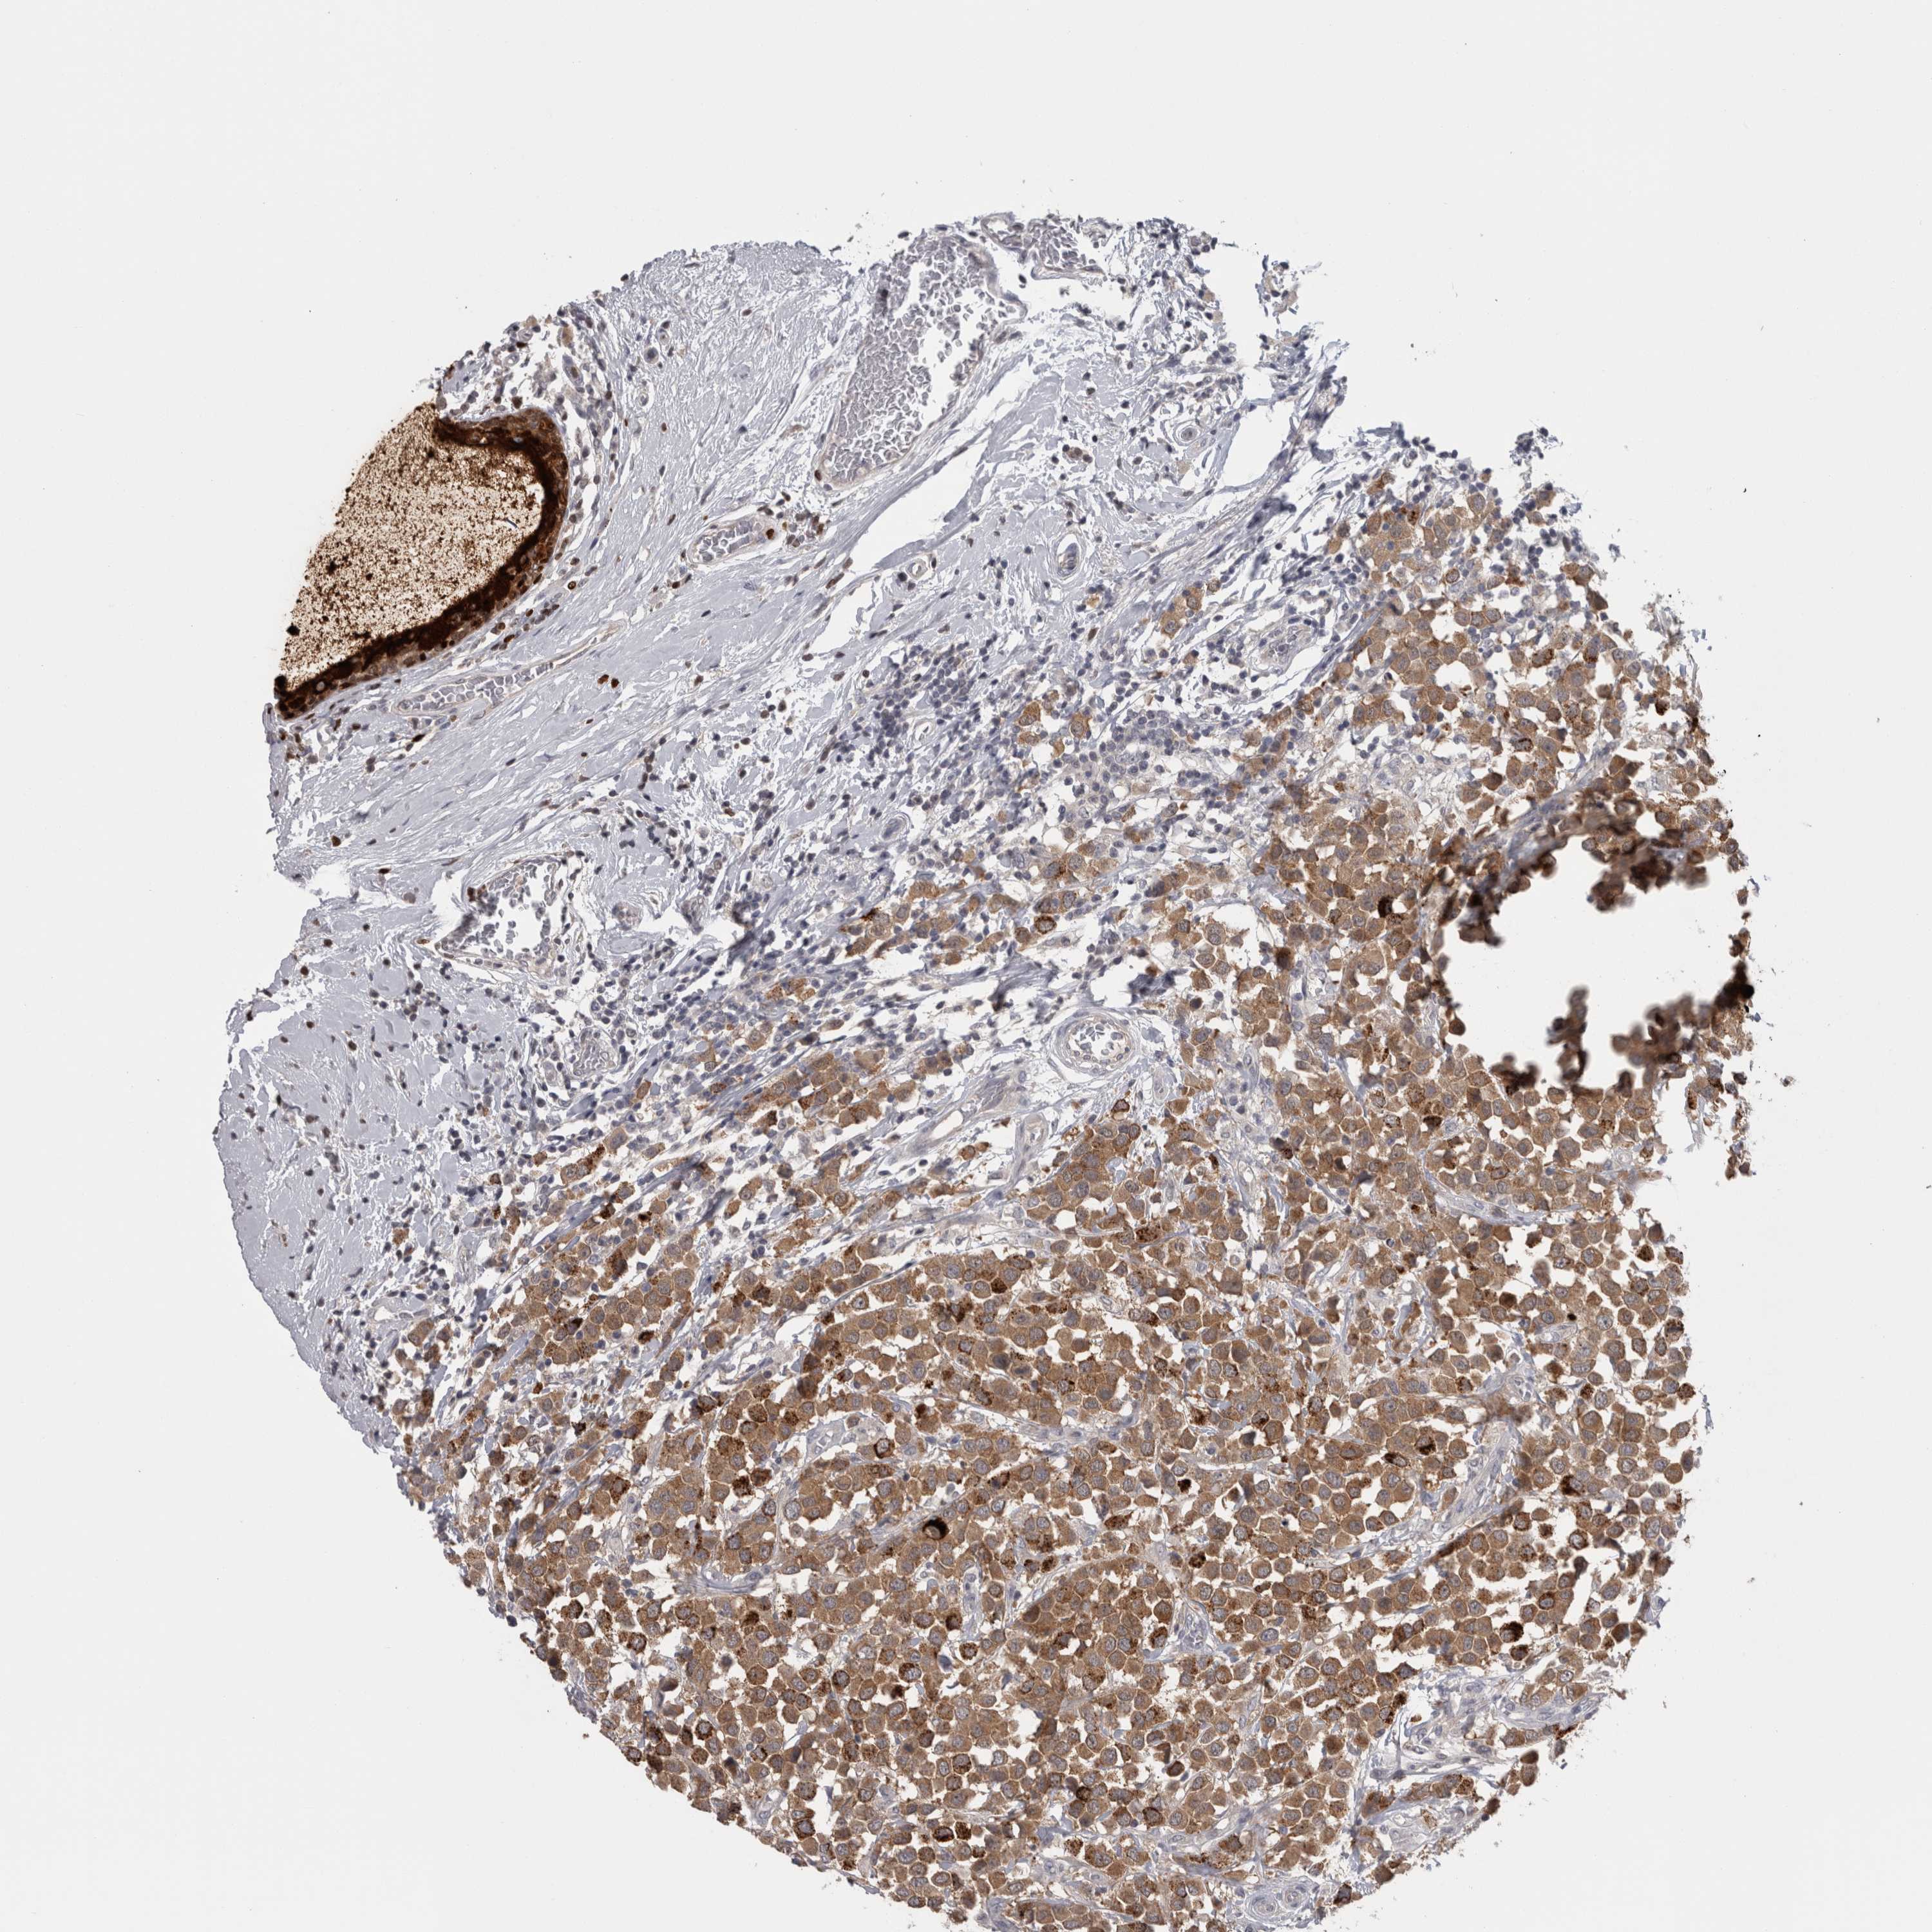

CANCER BREAST CANCER Show tissue menu

BRCA TCGA BRCA VALIDATION PROTEIN EXPRESSION

Breast cancer

Human cancer

Breast invasive carcinoma